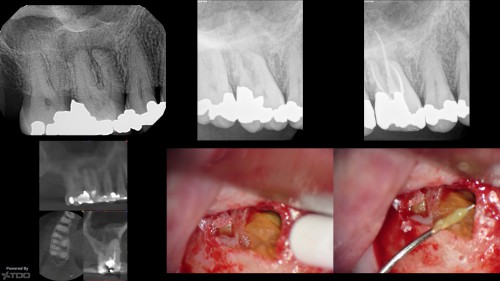

Cracked lower second molar

By Viraj Vora / August 1, 2018

Yesterdays complete. Findings were a DMR crack with no associated isolated probings and recurrent caries […]